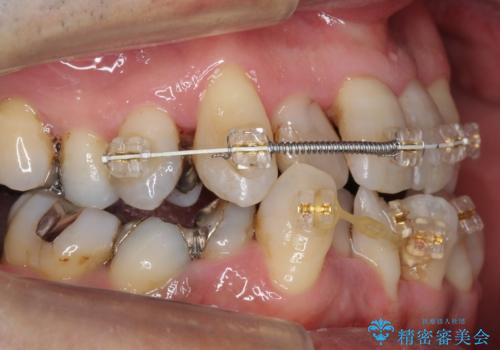

前歯の部分矯正を行い受け口を改善しました。

奥歯まで動かそうとすると顎の手術の適応になってしまうため、奥歯はそのままにして前歯のかみ合わせを改善しました。

また、奥歯はインプラント治療を行い、矯正で下の前歯を後ろに下げるのに使用しています。